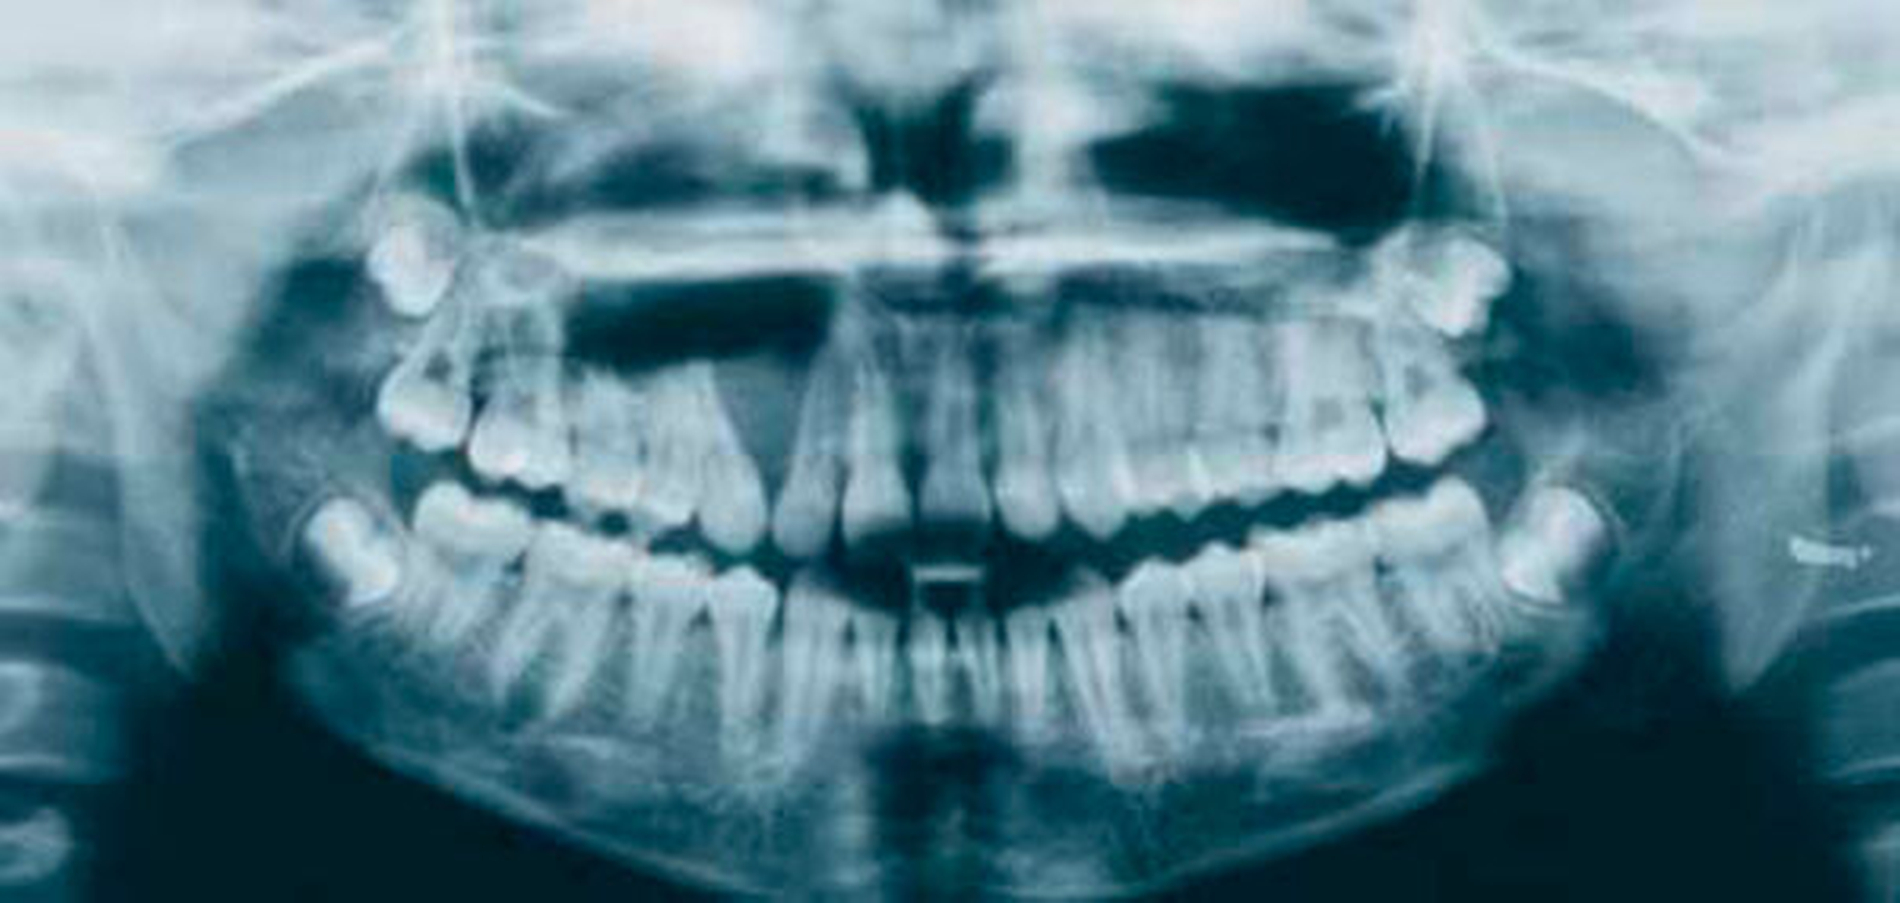

Die klinische und pathohistologische Evidenz spricht überzeugend dafür, dass Zysten im „Globulomaxillären Bereich“ radikuläre Zysten, laterale Parodontalzysten, odontogene Keratozysten [Christ, 1970], kalzifizierende odontogene Zysten, adenomatoide odontogene Tumore [Rosenberg & Cruz, 1963; Giansanti et al., 1970; Khan et al., 1977], odontogene Myxome [Rud, 1964; Taicher & Azaz, 1977], Ameloblastome [Aisenberg & Inman, 1960], zentrale Riesenzellgranulome oder hämorrhagische Knochenzysten [Peters & Wassow, 1968] sind (Abb. 6 bis 13).

Heute wird der Begriff „Globulomaxillär“ nicht mehr für eine eigene Entität, sondern für die anatomische Lokalisation einer Läsion verwendet, die im Oberkiefer zwischen dem lateralen Schneidezahn und dem Eckzahn vorkommt, und die erst nach eingehender klinischer, radiologischer und histopathologischer Untersuchung definitiv diagnostiziert werden kann.